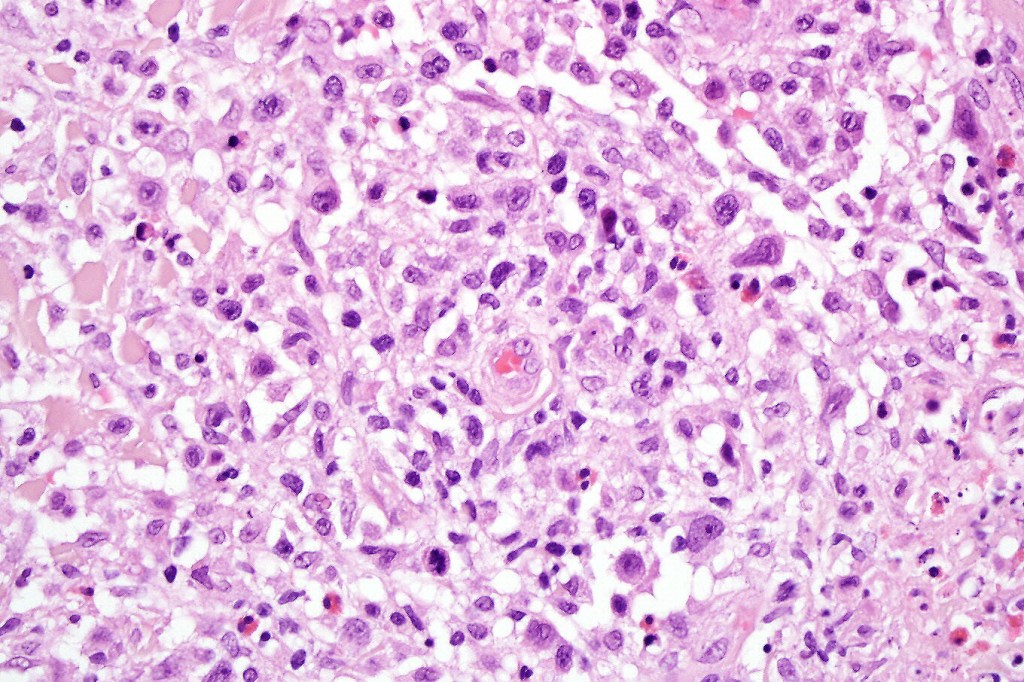

•Type A: 75-80%, wedge shaped infiltrate with base uppermost, large, anaplastic cells with abundant cytoplasm and vesicular nuclei containing prominent nucleoli, can resemble Reed-Sternberg cells, conspicuous mitoses & background infiltrate of lymphocytes, plasma cells, histiocytes, neutrophils & eosinophils

•Type C: 7-10% nodular infiltrate similar to primary cutaneous anaplastic large cell lymphoma

•Mixed variants are not uncommon